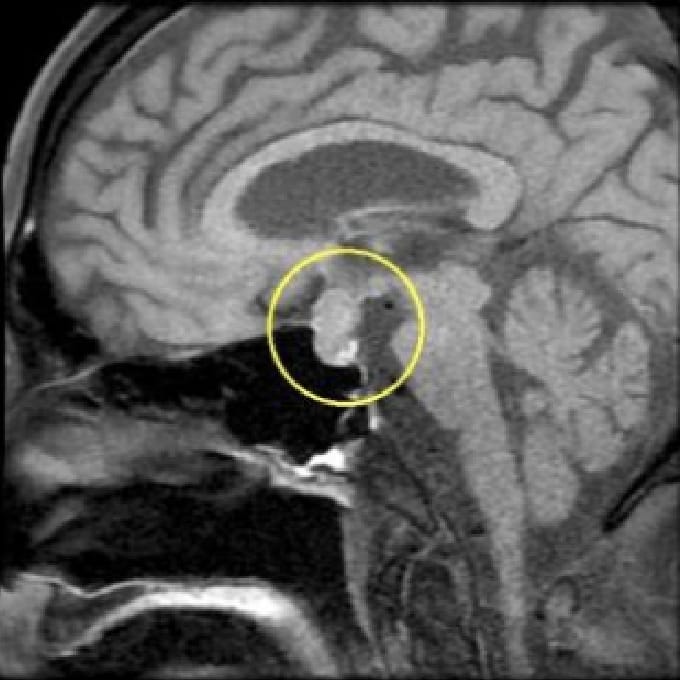

下垂体腫瘍

MRIは、脳の断面画像を撮影し、脳そのものの状態を確認する検査です。X線を使用せず、脳梗塞の痕跡(無症候性を含む)や出血の跡、腫瘍などの異常がないかを調べます。MRAはMRIの撮影法の一つで、脳や頸部の血管を画像として写し出し、血管の形や流れの状態を確認する検査です。未破裂脳動脈瘤の疑い、血管の狭窄・閉塞など、脳卒中リスクにつながる所見の確認に役立ちます。